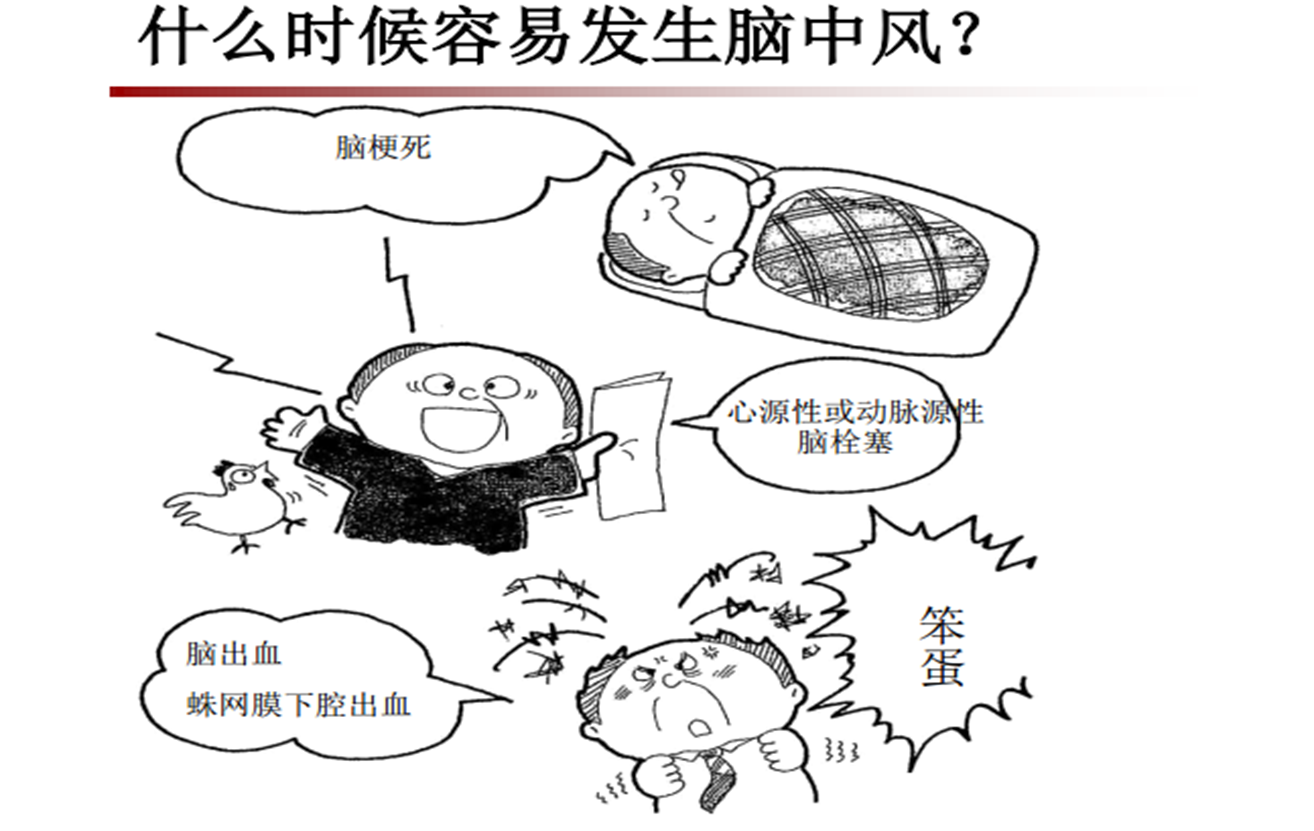

二、老百姓常常说脑中风,根据我国1986年的分类方法,脑卒中分类如下:

Ⅰ 脑梗死:1.脑血栓形成 2.脑栓塞3.腔隙性脑梗死 4.血管性痴呆

II颅内出血1.脑出血 2.蛛网膜下腔出血 3.硬膜外血肿 4.硬膜下血肿

注意:根据FAST是无法判断脑出血还是脑梗死的,需要快速到达最近的卒中中心,通过头颅CT去鉴别。

六、到达卒中中心后,会首先通过头颅CT鉴别脑出血及脑梗死。